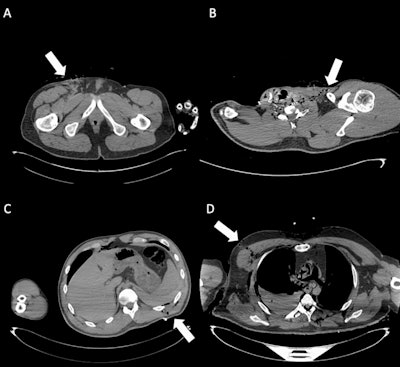

Organ injuries. (A) Axial CT scan shows traumatic injury to the bi-lobar liver parenchyma (white arrow). Moderate postmortem decomposition is also evident, with heterogeneous intraparenchymal gas distribution. (B) Cross-sectional CT image demonstrates a laceration of the right kidney (white arrow), consistent with penetrating trauma. (C) Axial CT slice shows a pericardial lesion (white arrow), with small gas bubbles in the anterior pericardial region, indicative of traumatic pericardial injury. (D) CT image highlights a laceration of the right middle lobe (white arrow), associated with pulmonary contusion, omolateral pneumothorax, and bilateral pleural effusion. In the assessment of organ injuries, inter-reader agreement was only moderate (Fleiss’ kappa = 0.52). Sensitivity was again limited among less forensic-experienced readers (31% and 51.7%), reflecting the interpretative complexity and reduced diagnostic accuracy of postmortem CT in this setting.